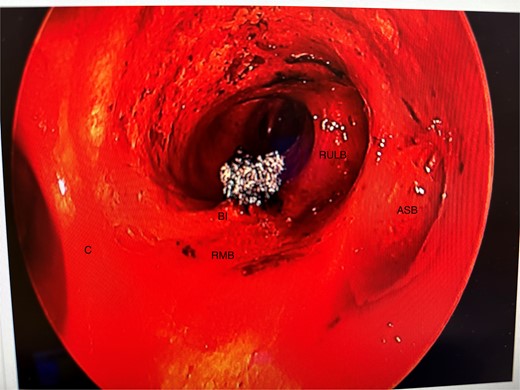

She initially underwent a rigid bronchoscopy, biopsy of the endobronchial tumour, cryoablation, and argon plasma for debulking. On direct visualization with the telescope the tumour was polypoid and was arising from the membranous portion of the right main bronchus (RMB) (Fig. 2).

Initial rigid bronchoscopy showing a polypoid mass originating from the membranous portion of the right main bronchus; BI, bronchus intermedius; RMB, right main bronchus.